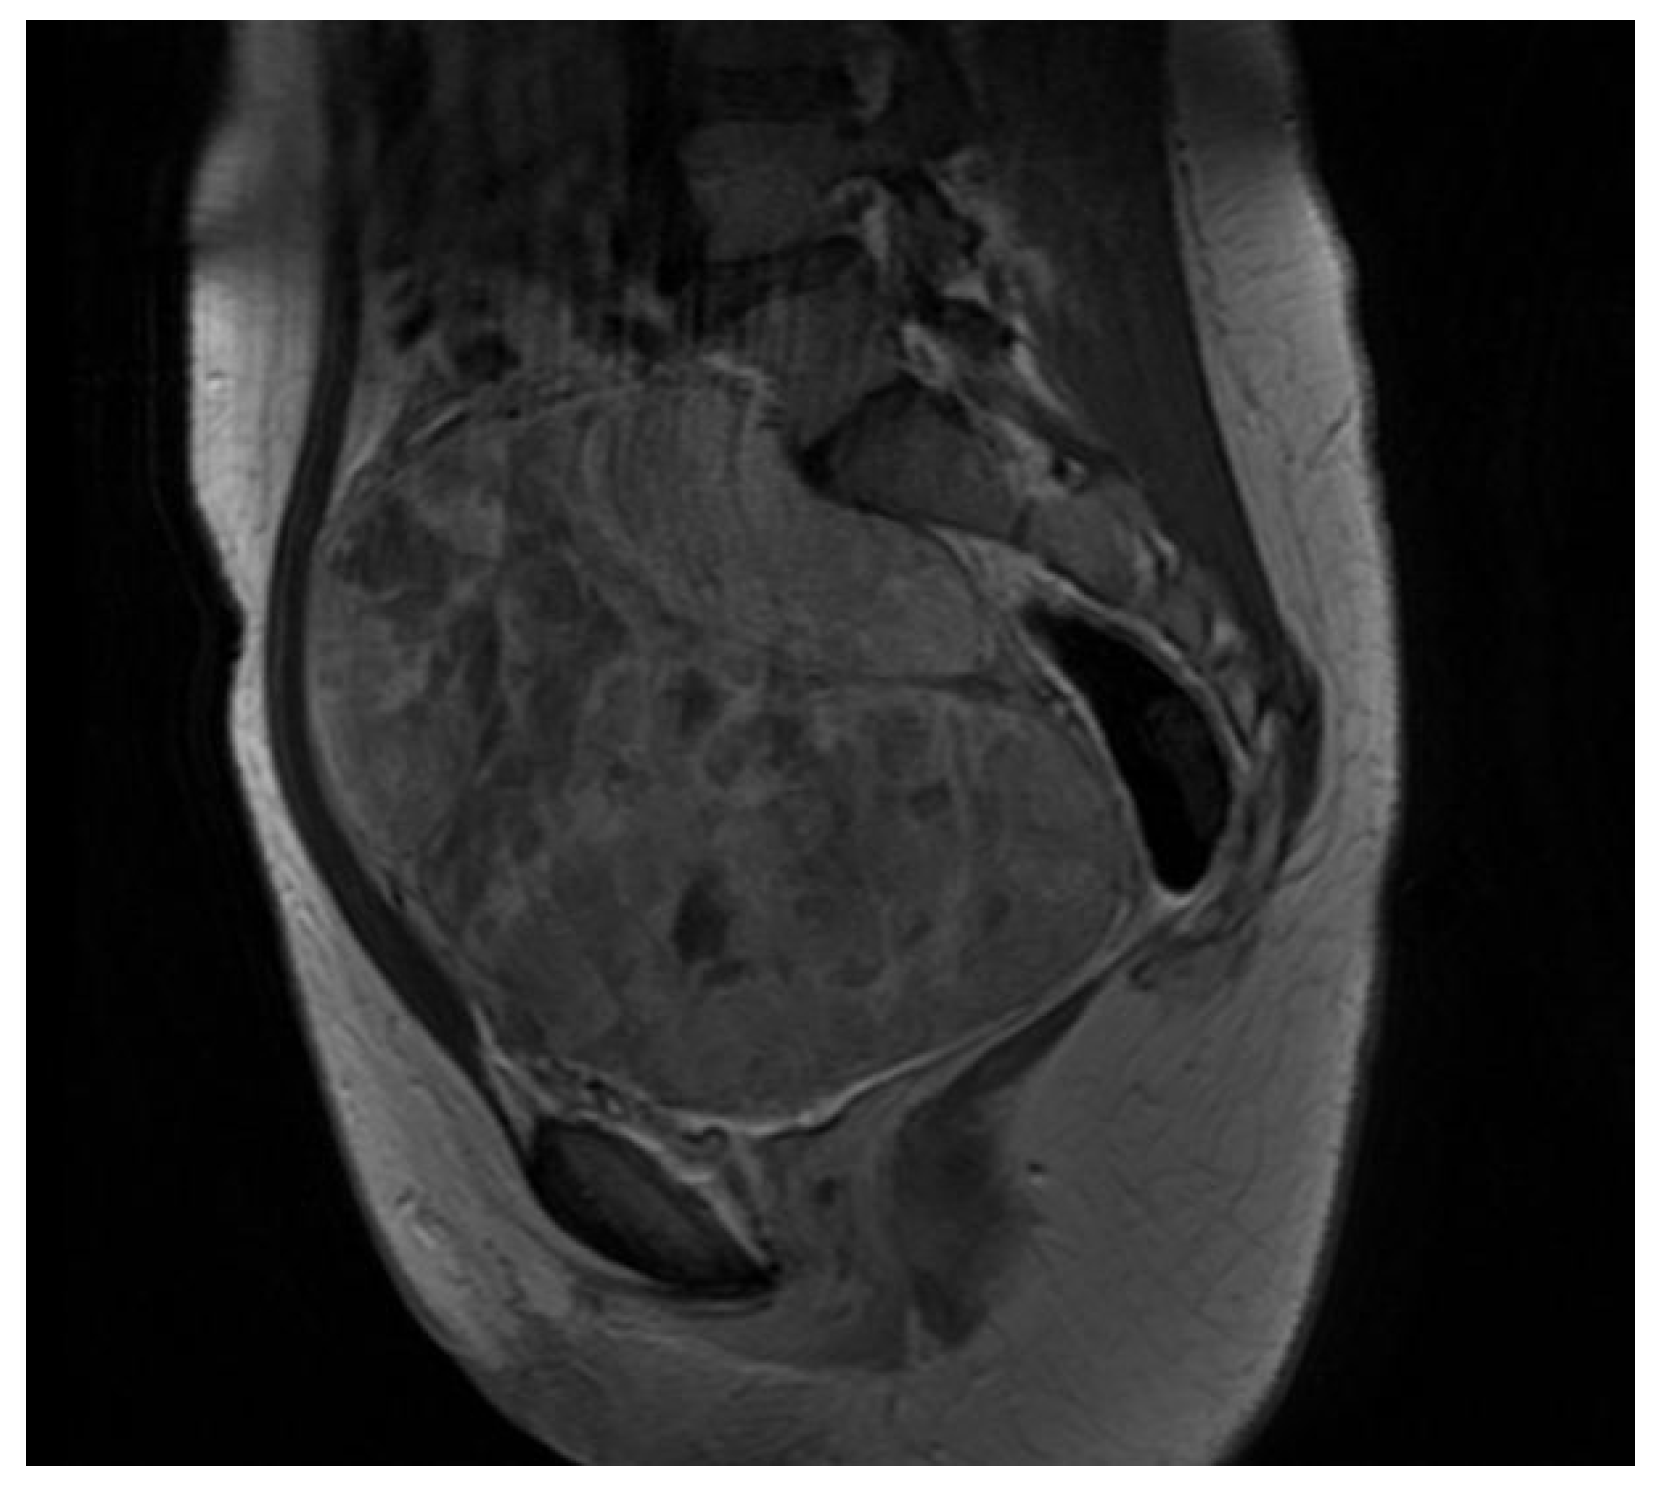

2. Case Presentation